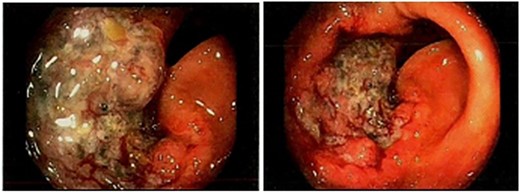

An 89-year-old male underwent an elective right hemicolectomy for transverse colon T3N0MX adenocarcinoma, diagnosed following colonoscopy (Fig. 1). Intraoperative findings revealed a distal synchronous mass in the transverse colon, and a classical extended right hemicolectomy was performed without the need for retroperitoneal mobilization.